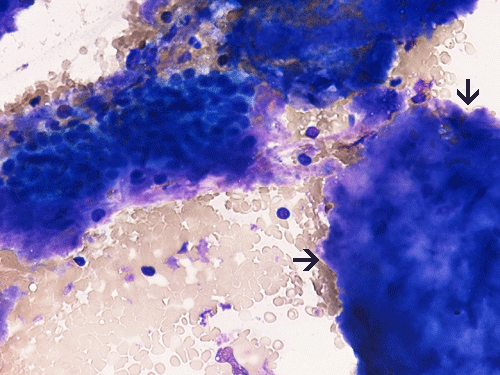

Clumps of amorphous substances with hypocellularity are noted with DiffQuick stain (arrows in Panel A) and Papanicolaou stain (arrows in Panel B). Normal glandular structures are also seen these preparations (Panel A and B). These amorphous substance stains orange on Congo red stain (Panel C and E) which gives a birefrigence under polarized light (Panel  D and F are corresponding images of Panel C and E). No tumor tissue is identified.

Primary amyloidosis tends to involve the heart, gastrointestinal tract, nerves, skin, tongue, eye, and respiratory system. Secondary amyloidosis tends to involve the kidneys, liver, spleen, lymph nodes, adrenals, and thyroid. Symptomatic amyloidosis of the head and neck is a rare but well documented condition  3, 4, 5, 6, 7. Most cases in this region involve one organ, without evidence of generalized involvement. The cytologic diagnosis of unexpected amyloidosis in the head and neck region can be challenging. Amyloid can be misinterpreted as keratin debris, colloid, chondroid or basement membrane material. Salivary gland amyloidosis is most often secondary and can mimic Sjogren’s syndrome and also pleomorphic adenoma because of the amorphous appearance of amyloid. Amyloidosis involving the major salivary gland in the form of a mass is rather uncommon and often present as diffuse or focal, bilateral enlargement of salivary glands. Variable amounts of acellular, eosinophilic extracellular material stains pale red with Congo red stain, and exhibits a characteristic apple-green birefringence under polarized light. The remainder of the smear is often hypocellular, with scant or absent acinar cells, and scattered clusters of ductal epithelial cells such as are seen in chronic sialadenitis.